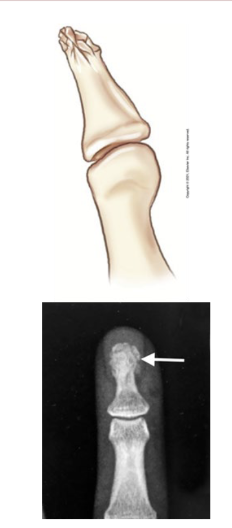

What type of fracture is this?

Tuft/Burst

What is a tuft/burst fracture?

Caused by crushing blow to distal finger or thumb (slamming in a door/hammer)